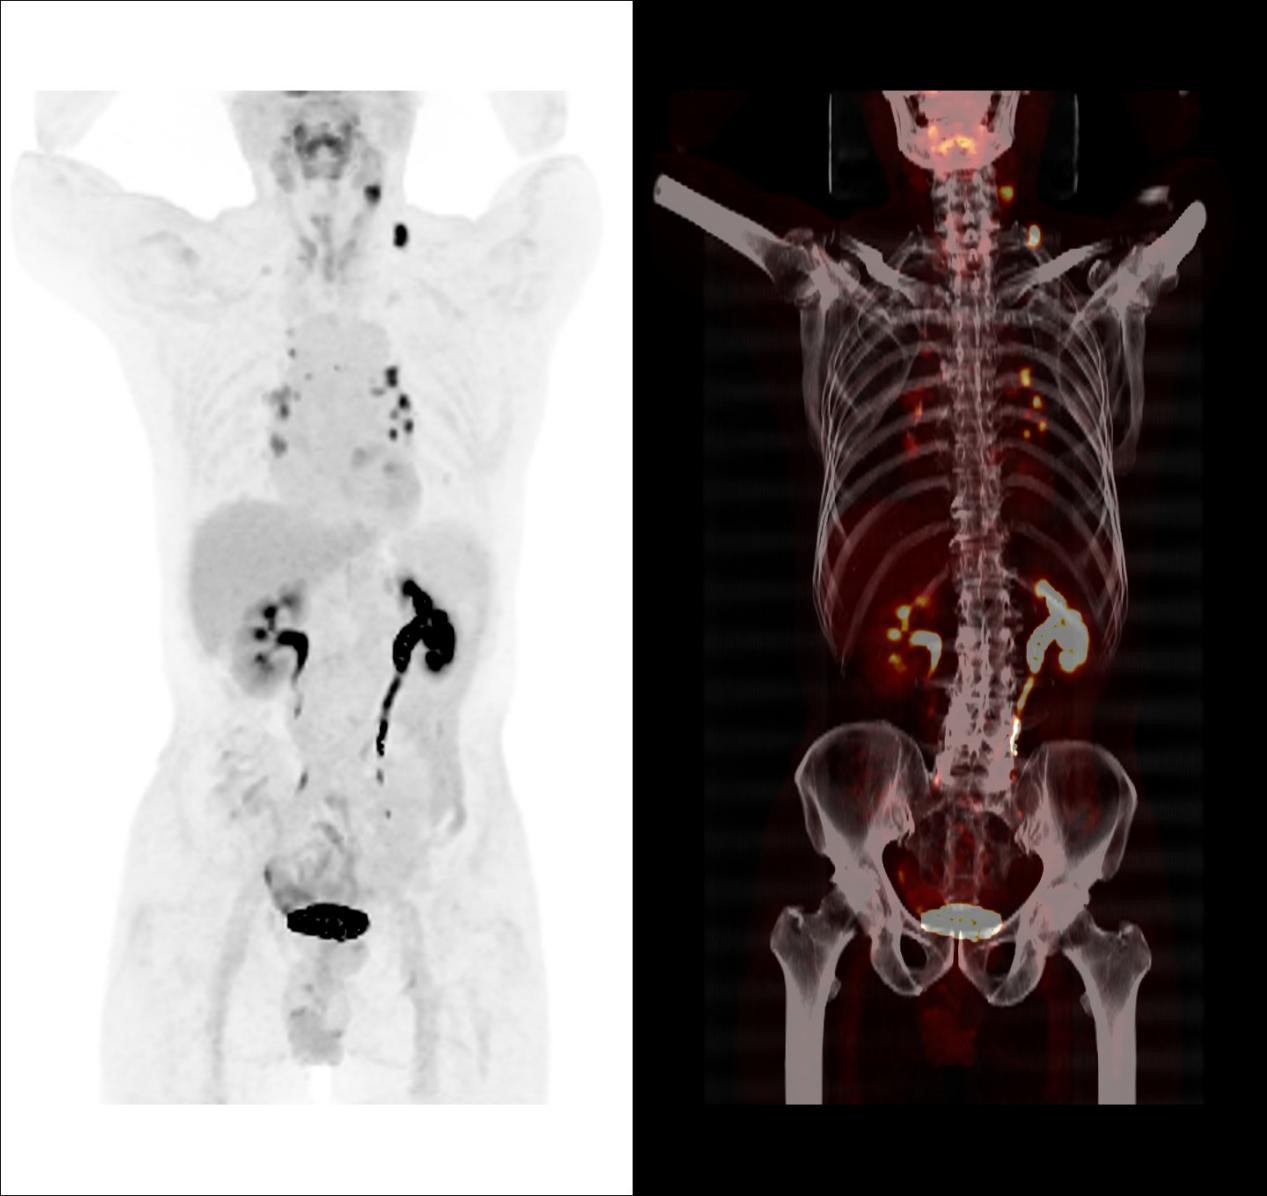

因此,临床医生给患者进行了传统的颈胸部增强CT检查以了解术后颈部情况,并试图寻找可能存在的原发病灶,但令人遗憾的是,增强CT并没有发现原发灶及转移相关证据。于是,医生决定给患者做一个全身PET/CT检查。

对于贺老伯来讲,超声及颈胸部增强CT检查均未能发现颈部、纵隔及肺门异常淋巴结,而PET/CT准确地找到这些异常淋巴结,就像多盏灯将这些隐藏的可疑淋巴结点亮一样,让可疑病灶无处遁形,为临床确定精准治疗方案提供帮助。